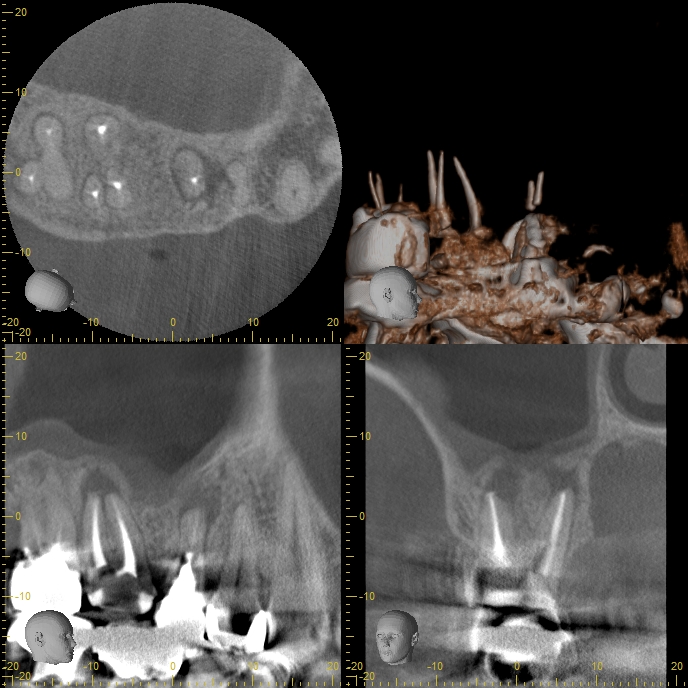

初診時CT画像。右上5番、6番、7番の根尖(こんせん:歯根の先端)に、根尖性歯周炎(根尖病巣)による黒いレントゲン透過像を認める。6番の根尖部の骨が吸収(欠損)し、上顎洞との交通を認める。上顎洞は上部にいたるまでレントゲン不透過性が亢進し(白くなっている)、顕著な上顎洞炎の所見を認める。耳鼻科による診査・診断のもと、すでに上顎洞炎の手術が予定されていた。手術に不安があったため、手術の前に歯の診査を希望し来院された。